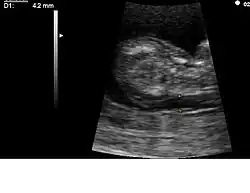

| Przezierność karkowa/badanie wolnej jednostki beta hCG/PAPPA | 11–13,6 | 91%[a] | 5%[a] | W badaniu wykorzystuje się technikę ultrasonografii do zmierzenia przezierności karkowej w połączeniu z badaniem wolnej beta hCG i PAPPA (ang. pregnancy-associated plasma protein A). Amerykańskie National Institutes of Health potwierdziło, że to badanie w pierwszym trymestrze ciąży jest bardziej dokładne niż metody przesiewowe w drugim trymestrze[25]. |